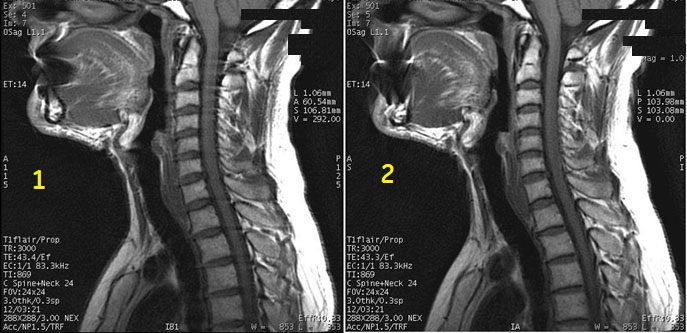

Figure 3. Frequency A/P and S/I comparison

Table 3. Image legend

NumberDescription

1Frequency A/P with streaks in image

2Frequency S/I with no streaks in image

• To swap phase and frequency rotate the FOV on the sagittal view of the localizer.